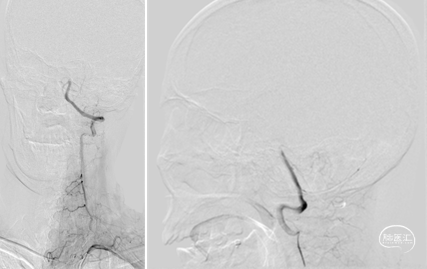

术前造影,BA近端闭塞。

术前造影,LC7次全闭塞。

术前造影,RICA 通过交通动脉向左侧颈内动脉及基底动脉尖代偿供血。